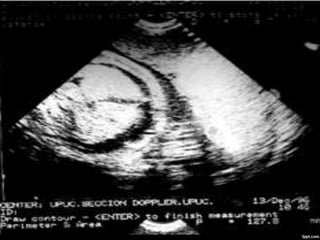

CARACTERÍSTICAS

ECOGRÁFICAS

ASCITIS

•DESDE PEQUEÑAS COLECCIONES.

•ACUMULACIONES MAYORES.

DERRAME PLEURALY O

PERICARDICO.

•UNILATERALES.

• BILATERALES.

•PEQUEÑOS.

•GRANDES.

DERRAME PLEURAL

EDEMA SUBCUTÁNEO

•GENERALIZADO.

•LOCALIZADO.

•LIMITADO A LA PARTE SUPERIOR O

INFERIOR DEL CUERPO.

EDEMA DE LA

PLACENTA

•GROSOR MAYOR A 6 CM PARA EL TERCER

TRIMESTRE

DIAGNÓSTICO

ECOGRÁFICO

PRESENCIA DE DOS O MÁS DE LOS

SIGUIENTES HALLAZGOS:

•ASCITIS FETAL

•DERRAME PLEURAL

•DERRAME PERICÁRDICO

•EDEMA SUBCUTÁNEO (MAYOR A 5 MM)

•HIGROMA QUÍSTICO

•POLIHIDRAMNIOS (50-75%)

•ENGROSAMIENTO DE LA PLACENTA

(MAYOR A 6 CM)

HALLAZGOS ECOGRÁFICOS: ASCITIS,

DERRAME PLEURAL, EDEMA SUBCUTÁNEO,

EDEMA PLACENTARIO.